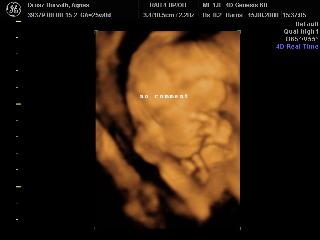

Pannaanya: tök jók a 4D-s képek! Siófok-Sóstó? Na az tőlünk kb. 7 km, ha olvasod és van kedved, akár össze is futhatnánk